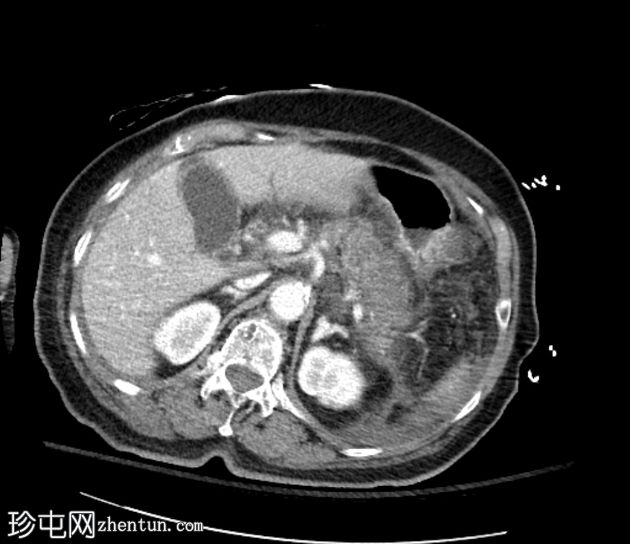

冠状位增强扫描(门静脉期)

胰腺弥漫性肿大,实质呈不均匀强化,胰头、胰体远端和胰尾可见大片无强化坏死区域(坏死胰腺实质>50%)。胰周脂肪间隙模糊,胰周、肠系膜根部、左右肾前间隙可见多发性急性坏死灶(ANC)。

门静脉、脾静脉和肠系膜静脉通畅。未见血管并发症。

轻度腹腔和盆腔腹水,伴大网膜和腹膜增厚及模糊影。

胃、十二指肠、小肠和大肠壁增厚,可能为反应性改变。

该病例表现为急性坏死性胰腺炎,伴大面积无强化实质坏死(>50%胰腺实质),以及急性胰周坏死积液(ANC持续时间<4周)。Balthazar评分E级,胰腺坏死>50%,CT严重程度指数10。胰酶升高确诊。患者紧急入住ICU。